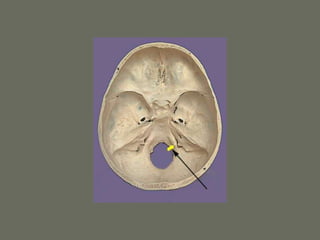

The Skull